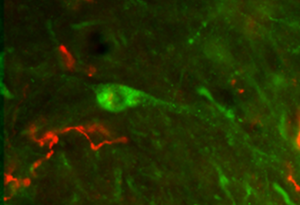

Reticulospinal axon (red) and parvalbumin labeled interneuron (green) in the  Intermediate grey matter of the lumbar spinal cord (magnification 40x)

Following SCI, individuals who recover the ability to walk in the community have a greater risk of falling during daily activities, but the reason for this is poorly understood. During gait, as body weight is shifted on to one leg so the other leg can step through, the weight bearing leg bends as it accepts the weight. After SCI, changes to the activation of ankle muscles, particularly gastrocnemius, disrupt the control of this flexion during weight shift, which can lead to instability and/or collapse when loading the leg. Currently there are few rehabilitation interventions that address this deficit adequately, however, the task of walking downhill may offer a new strategy to address these functional deficits. This is because walking on declines leads to increased flexion of the leg during loading over a longer period of the gait cycle. This project investigates the biomechanical changes that occur during gait following SCI and the response to different rehabilitation interventions such as walking on level ground or on declined surfaces. In addition, ReMaP is investigating the role that descending motor pathways, especially those from the brainstem, may play in this disruption in biomechanics during weight shift and if the different rehabilitation interventions (training on level or declined surfaces) will facilitate plasticity within these pathways. This is done using tract tracing and immunohistochemical techniques to identify various axons and neurons in the lumbosacral spinal cord as shown in the picture below.